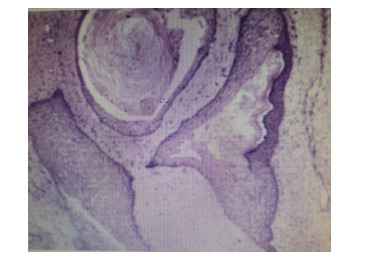

| 图 2 患者2019-06-04术后病理结果(示成熟性畸胎瘤,HE×40) |

1 资料与方法患者,女,33岁,因“急起胡言乱语、行为异常10 d”于2019年4月21日收治于杭州市第七人民医院。4月11日患者因工作压力大在单位突然情绪崩溃,胡言乱语,行为异常,后回家休息。在家中,患者间歇性通过哭泣、叫喊发泄情绪,彻夜不眠,大声咒骂,情绪异常激动,送至杭州市第七人民医院住院治疗。入院后查血常规、生化全套、甲状腺功能、头颅CT等无异常,诊断考虑:焦虑状态、精神障碍、分离转换障碍,给予奥氮平、丙戊酸钠、百忧解等药治疗,效果不佳。5月3日患者突然发热,体温最高达39.1℃,急查血常规:白细胞11.44×109/L,中性粒细胞8.32×109/L,C反应蛋白229.2 mg/L。生化:谷丙转氨酶143.8 U/L,谷草转氨酶78.9 U/L,肺CT示左肺上叶舌段及右肺中叶内侧段慢性炎症或纤维灶考虑。予头孢呋辛抗感染治疗,效果不佳。追问病史,患者诉7年前体检发现畸胎瘤,直径约2.7 cm,无不适,未治疗,后育二女,均无异常。急查腹部CT示:下腹部盆腔内巨大占位,肿瘤首先考虑,畸胎瘤可能性大:右侧附件区低密度灶; 盆腔少量积液。因患者感染控制不理想,精神症状稍好转,遂出院。至本地某三甲医院就诊,复查血常规:白细胞15.9×109/L,中性粒细胞12.62×109/L,C反应蛋白239.4 mg/L。生化:谷丙转氨酶117 U/L,谷草转氨酶69 U/L。凝血酶原时间14.6 s,D-二聚体5 520 μg/L。予头孢类抗生素静滴,体温控制不佳,并出现腹部绞痛。为求进一步诊治于2019年5月13日以“发热待查”入树兰医院感染科。患者入院后仍反复高热,炎症指标高,全腹平扫+增强CT示:双附件区及下腹腔多发占位,考虑多发畸胎瘤,较大病灶破裂可能,腹盆腔积液(图 1),头颅MRI无异常。5月16日组织感染科、胃肠外科、妇科、精神科等多学科会诊(MDT)。感染科认为患者目前双侧畸胎瘤伴破裂,腹腔继发感染明确,曾有精神神经症状,故尚需排除脑炎; 胃肠外科认为患者目前盆腔肿块卵巢肿瘤诊断明确,建议:⑴先确定脑炎与肿瘤的关系; ⑵手术治疗; ⑶若同结肠有关,术中同时处理。精神科认为患者短期出现言行异常、情绪不稳定、遗忘、烦躁等多种精神症状,在杭州市第七人民医院住院治疗期间,又出现了高热、意识障碍、痫性发作等情况,起病急,精神症状变化快,考虑患者精神症状可能与畸胎瘤有关,建议完善腰穿检查,排除自身免疫性脑炎(NMDA抗体)所致精神障碍。妇科认为患者已婚育,发现畸胎瘤7年,突发腹痛、精神症状、发热等,CT提示盆腔巨大包块,不排除畸胎瘤破裂感染粘连可能,建议:⑴患者目前不排除畸胎瘤与精神症状、自身免疫性脑炎相关,故完善NMDA抗体检测,如能明确则行双侧切除,术后相关激素替代治疗,如非自身免疫性脑炎,则术中尽可能保留卵巢功能。⑵控制感染,完善检查后转妇科手术治疗。5月19日查腰穿结果提示:脑脊液抗谷氨酸受体(NMDA型)抗体IgG+ 1∶10,诊断自身免疫性脑病明确,考虑患者精神症状与畸胎瘤关系密切,且畸胎瘤较前进展快,恶变可能,局部小破裂,腹腔感染明确。在感染科予抗炎、护肝、抗精神病等治疗后患者病情有所控制,5月21日转妇科进一步诊治。完善术前准备,于5月28日行“腹腔镜下双侧卵巢囊肿剥除术+左侧输卵管切除术+盆腔粘连分离术+肠粘连松解术”,术中见子宫前位,正常大,表面光滑,形态正常; 左侧卵巢冠囊肿增大约10 cm×11 cm×9 cm,与左输卵管一起顺时针扭转1.5圈,左侧输卵管增粗水肿。大网膜、乙状结肠和左侧卵巢冠囊肿致密粘连; 右侧卵巢分别见大小约3 cm×2 cm及2 cm×2 cm囊肿,右侧输卵管外观无殊。术中及术后病理均提示:⑴(左卵巢)成熟性畸胎瘤伴神经组织及坏死; ⑵(右卵巢)成熟性畸胎瘤(图 2)伴甲状腺肿。术后4 d,复查血常规+超敏C反应蛋白,白细胞计数3.7×109/L,中性粒细胞百分比58.8%,超敏C反应蛋白8.2 mg/L,患者恢复良好,停用抗生素。精神科会诊患者精神症状完全消失,接触交谈如常人。出院后随访:患者出院后未再服用精神类药物,继续免疫治疗[3]。随访1年,患者无明显精神症状,工作生活如常人。